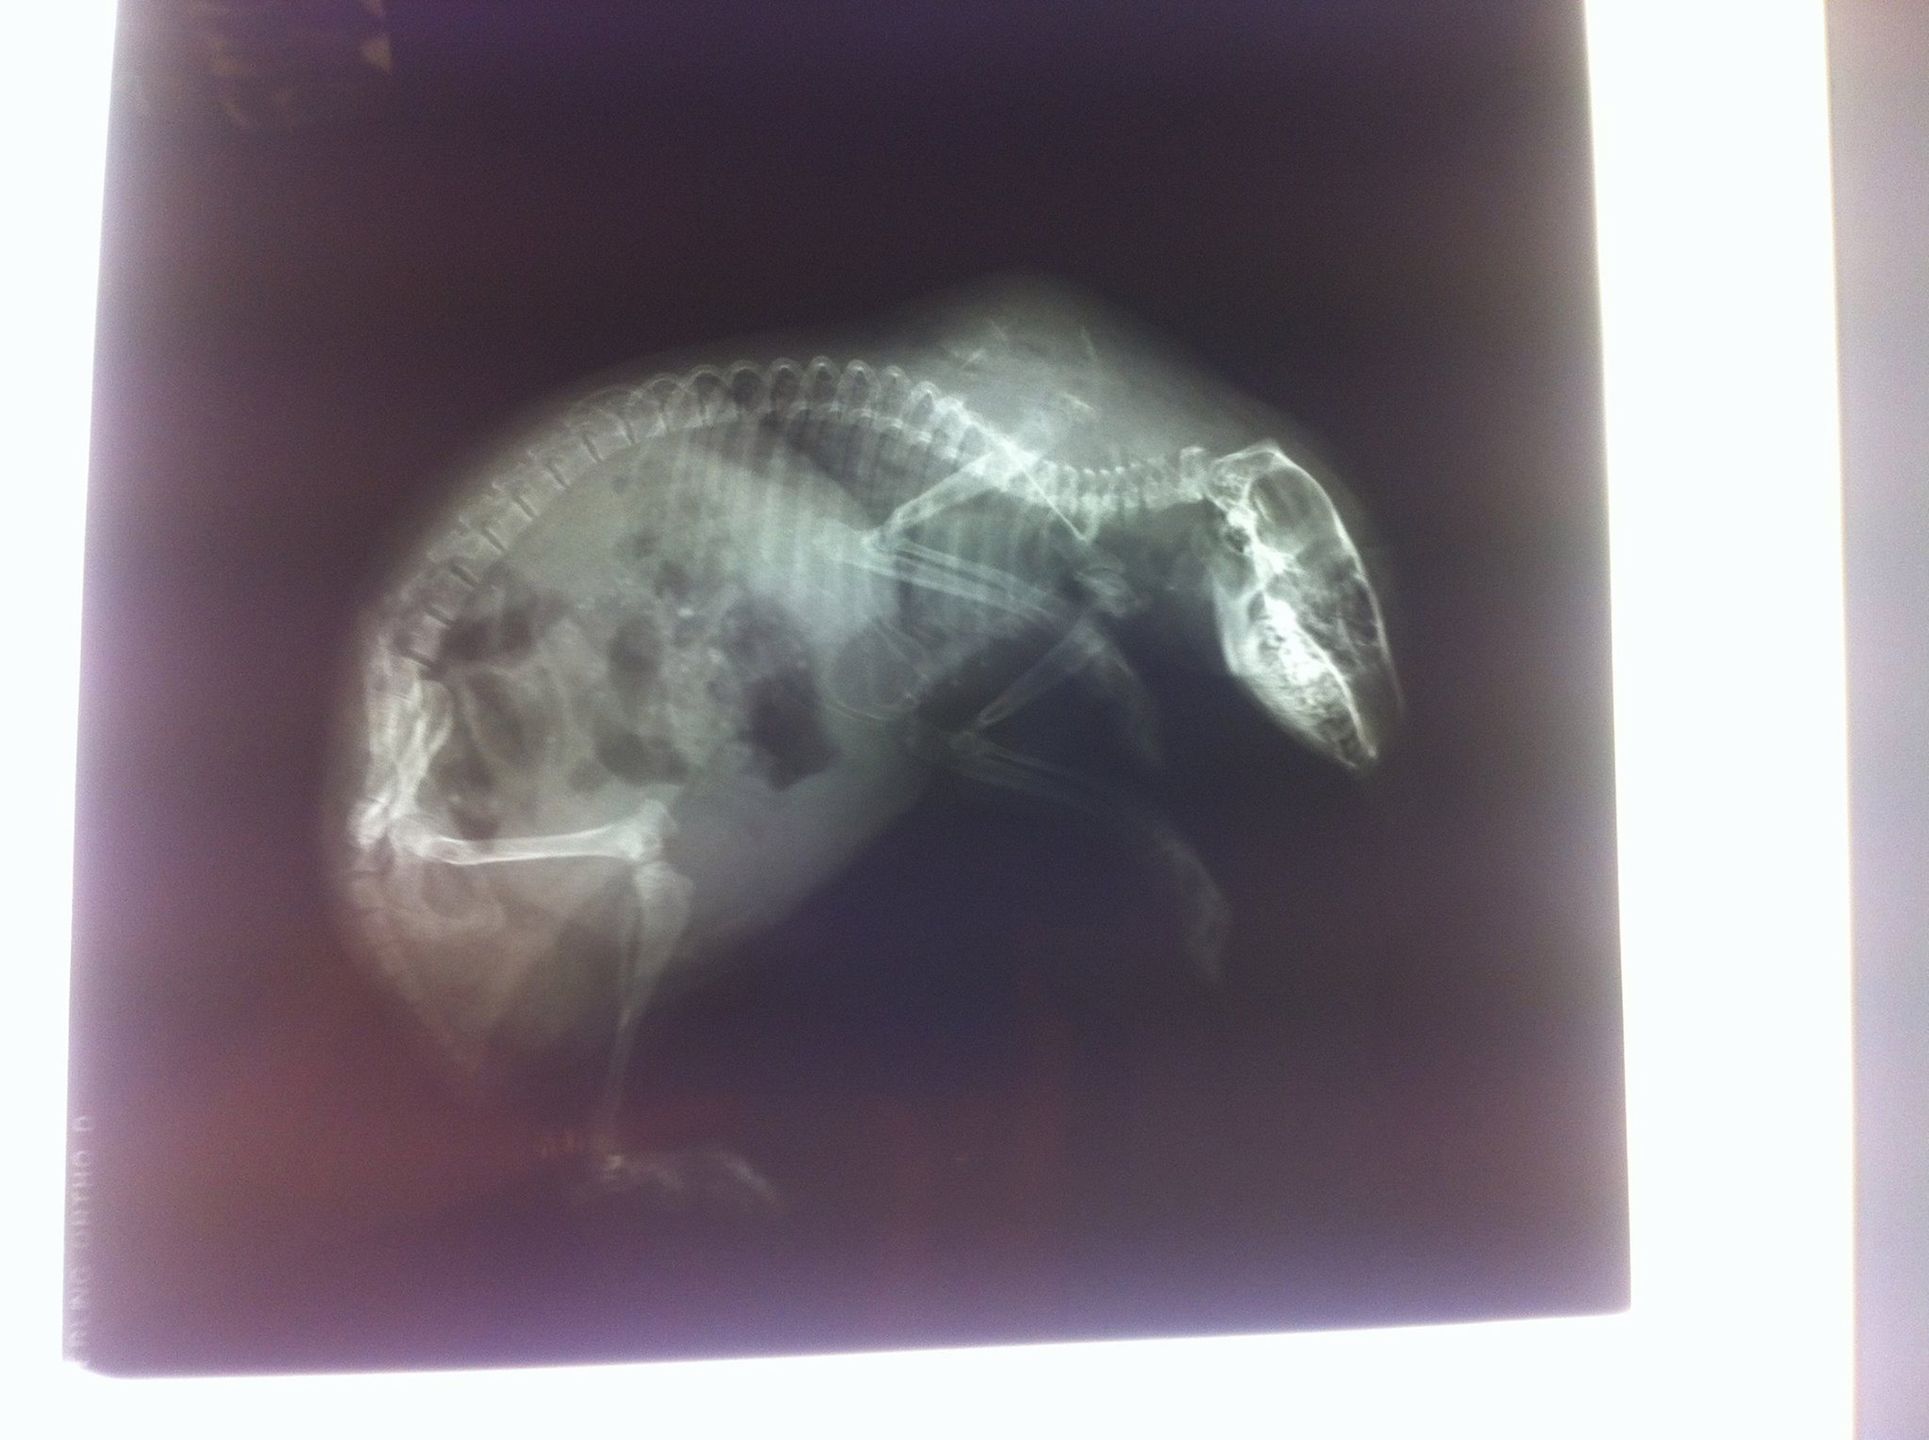

Niezwykły pacjent leczony jest w przychodni weterynaryjnej w brytyjskim Hertofdshire. Jeż Derek ma problem z łysieniem, które najprawdopodobniej jest wynikiem traumatycznego dzieciństwa.

Kiedy znaleziono go w jednym z ogrodów, był malutkim jeżykiem. Był wielkości chomika i miał na grzbiecie sporą ranę, więc weterynarze bali się się, że może zaatakować go ptak. Myśleli też, że brak kolców spowodowane jest jakąś bakterią albo pasożytem. Dopiero potem po wykonaniu szczegółowych badań okazało się, że malec łysieje.